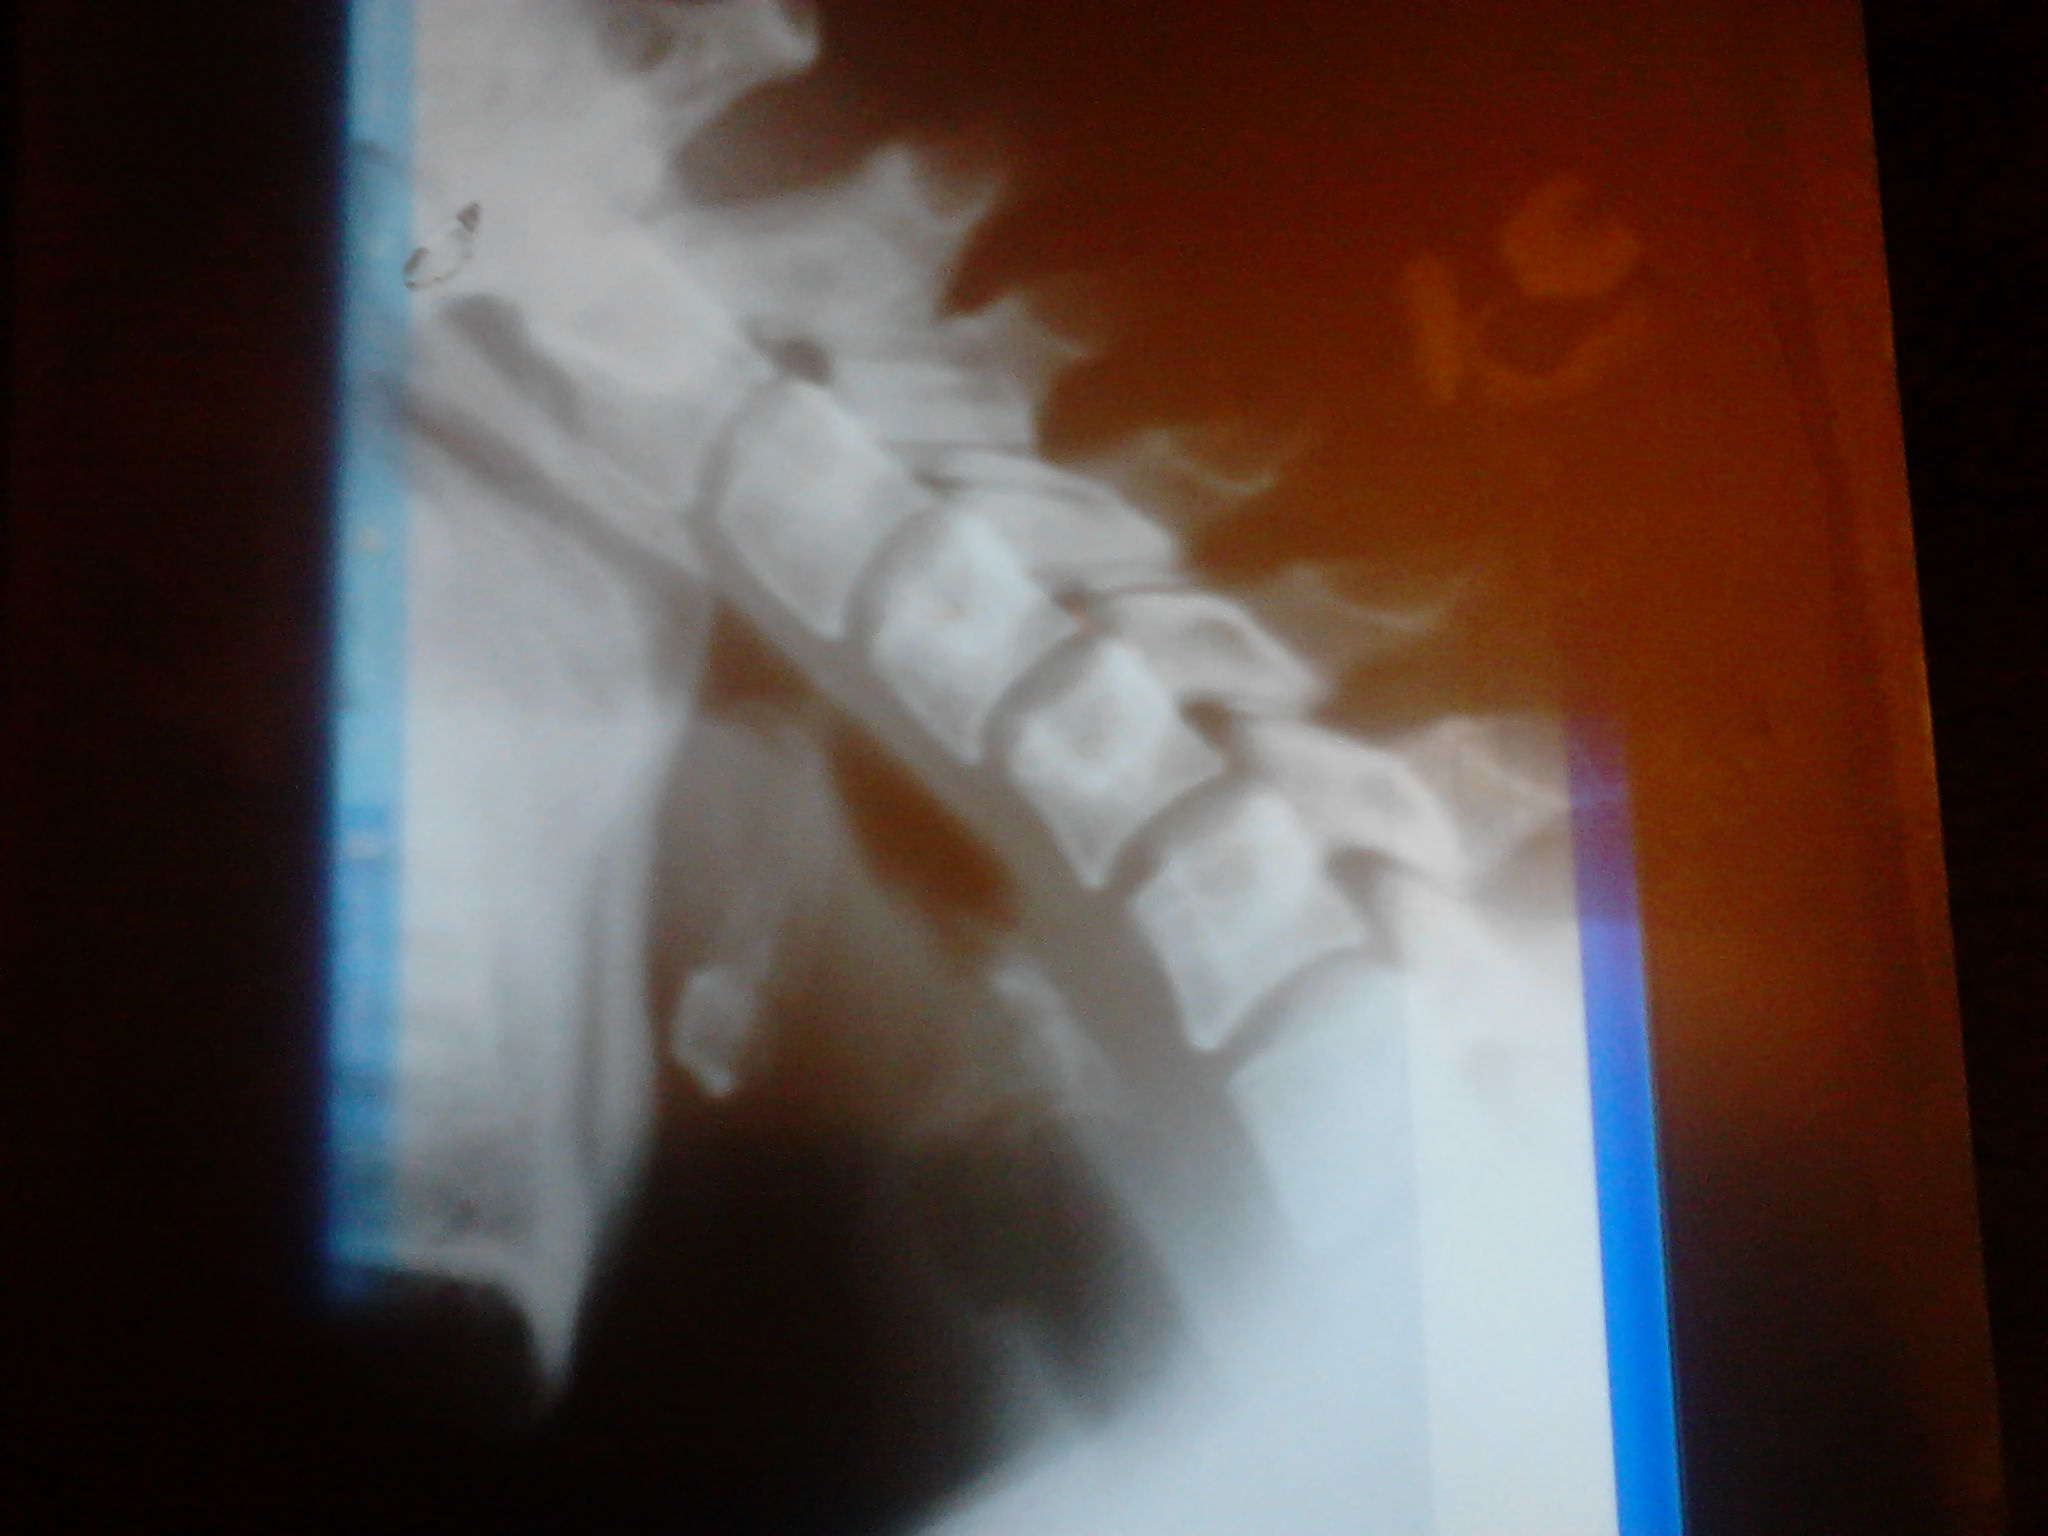

боль в шее...головная боль....головокружения...вегетативные кризы с повышением давления..мельканием мушек...парестезия рук...нистагм....преходящее нарушение мозгового кровообращения(с афазией и синкоп. состояние)

Аномалия Киммерле. Допплеровское исследование сосудов шеи делали?

Да делала...изменения при поворотах небольшие...посмотрите нестабильность...пож-та

Ну, раз это необходимо. Нестабильности (т.е такой, настоящей, больше 3мм смещение) нет. При сгибании - лестничный микроантелистез С2, С3, С4, С5; при разгибании - микрорентролистез С3, С4. Еще хорошо бы обычный боковой снимок, для оценки статики.